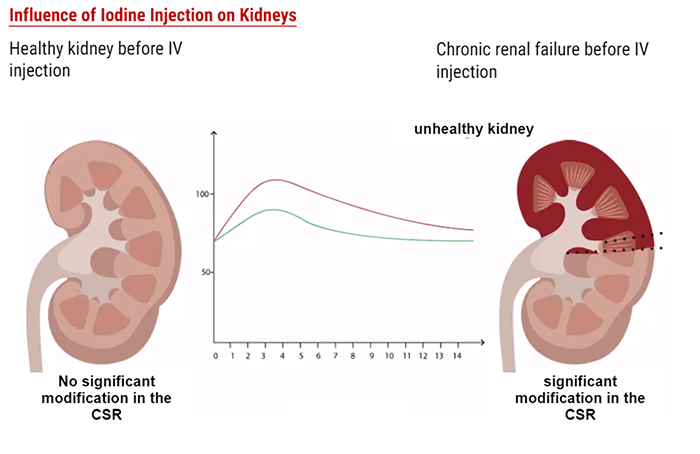

Influence of an Iodine Injection on Kidneys

Left Side: Healthy kidney before IV injection – Right Side: Chronic renal failure before IV injection

Nephropathy

Depending on the Glomerular Filtration Rate (expressed in ml/min/1,73m2), we can distinguish 5 stages for the kidney function condition. For children and elderly patients, the clearance is low therefore it is very important to perform an analysis on a blood sample before injecting any contrast agent.